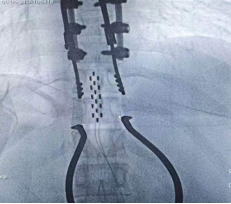

2026年1月30日,完善术前准备后,手术于全麻并全程电生理监测下进行,历经5小时苦战,顺利于腰膨大处置入外科电极一枚,双侧骶3孔各植入一根穿刺电极,连接2枚刺激器后埋置于皮下。手术实施顺利,术中X线检查植入位置良好。目前患者生命体征平稳,已开机测试,后期动态调整刺激参数,并结合非侵入式脑机接口锻炼。

成功植入565外科电极

双侧骶3孔顺利植入穿刺电极